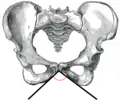

Angle sous-pubien masculin